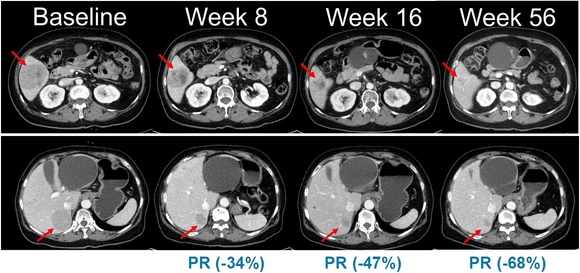

▲NRAS 돌연변이 흑색종 환자를 대상으로 진행된 벨바라페닙과 코비메티닙 병용요법 임상시험에서 시간 경과에 따른 병변 변화가 관찰된 복부 CT 영상. / 사진=미국임상종양학회(ASCO) 2021 구연 발표

이번 임상 2상은 총 45명의 환자를 대상으로 표적 항암신약 벨바라페닙과 MEK 억제제인 코비메티닙(Cobimetinib) 병용요법의 유효성과 안전성을 평가하기 위한 다기관, 단일군 시험으로 진행된다.